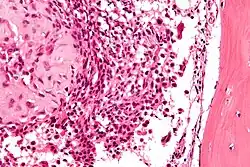

| Micrograph of a chondroblastoma. H&E stain. | |

Chondroid differentiation is a common feature of chondroblastoma.[1][4][6] A typical histological appearance consists of a combination of oval mononuclear and multi-nucleated osteoclast-type giant cells.[1][3][4] However this is not a prerequisite for diagnosis, as cells with epithelioid characteristics have been observed in lesions of the skull and facial bones.[4] A "chicken-wire" appearance is characteristic of chondroblastoma cells and is the result of dystrophic calcification that may surround individual cells.[1][5] Although, calcification may not be present and is not a prerequisite for diagnosis.[1][3][4] Mitotic figures can be observed in chondroblastoma tissue but are not considered atypical in nature, and therefore, should not be viewed as a sign of a more serious pathology.[1][4] There is no correlation between mitotic activity and location of the lesion.[4] Furthermore, the presence of atypical cells is rare and is not associated with malignant chondroblastoma.[1][6]